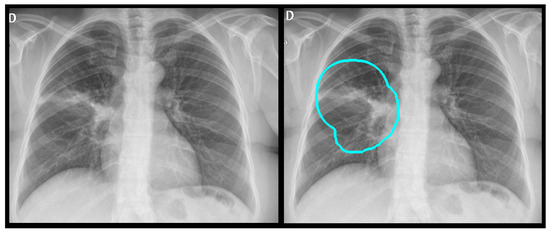

Representative Grad-CAM overlays are shown in Figure 3, Figure 4, Figure 5 and Figure 6, illustrating several different types of pathologies. These visualizations demonstrate where the algorithm focuses attention on the appropriate pathological regions, thereby reinforcing the validity and interpretability of the proposed pipeline.

3.3. Error Analysis

An analysis of the algorithm’s false negatives revealed a nuanced performance profile, where a specific miss did not always equate to a complete system failure. Across the board, a substantial number of cases with a false negative for a particular pathology were nevertheless correctly identified as abnormal by the general “yes-finding” classifier or had other co-occurring true positive pathologies. For example, out of 38 false negatives for opacity, the algorithm correctly identified the exam as abnormal in 25 cases. In many instances of a missed finding, the algorithm successfully detected other pathologies within the same study. Misclassification was another notable source of error, where an existing pathology was detected but incorrectly labeled, such as opacities being predicted as masses or nodules (Figure 4). Radiologist review of these false-negative cases frequently noted findings that were “subtle,” “small,” “doubtful,” “seen on lateral image only,” or “non-specific.” In other cases, the algorithm correctly identified a more critical finding, like a large pleural effusion, while missing a secondary, less significant pathology (Figure 3). Figure 9, Figure 10 and Figure 11 illustrate false negative cases for opacity, pneumothorax, and nodule, respectively. This highlights the inherent limitations and inevitable failures of this kind of system.

Figure 4. A true positive example of a nodule/mass (left) and its bounding box generated image (right). In this case, the report indicated opacity; however, the algorithm classified as a mass.

Figure 5. A true positive example of opacity and consolidation (left) and its contour line generated image (right).